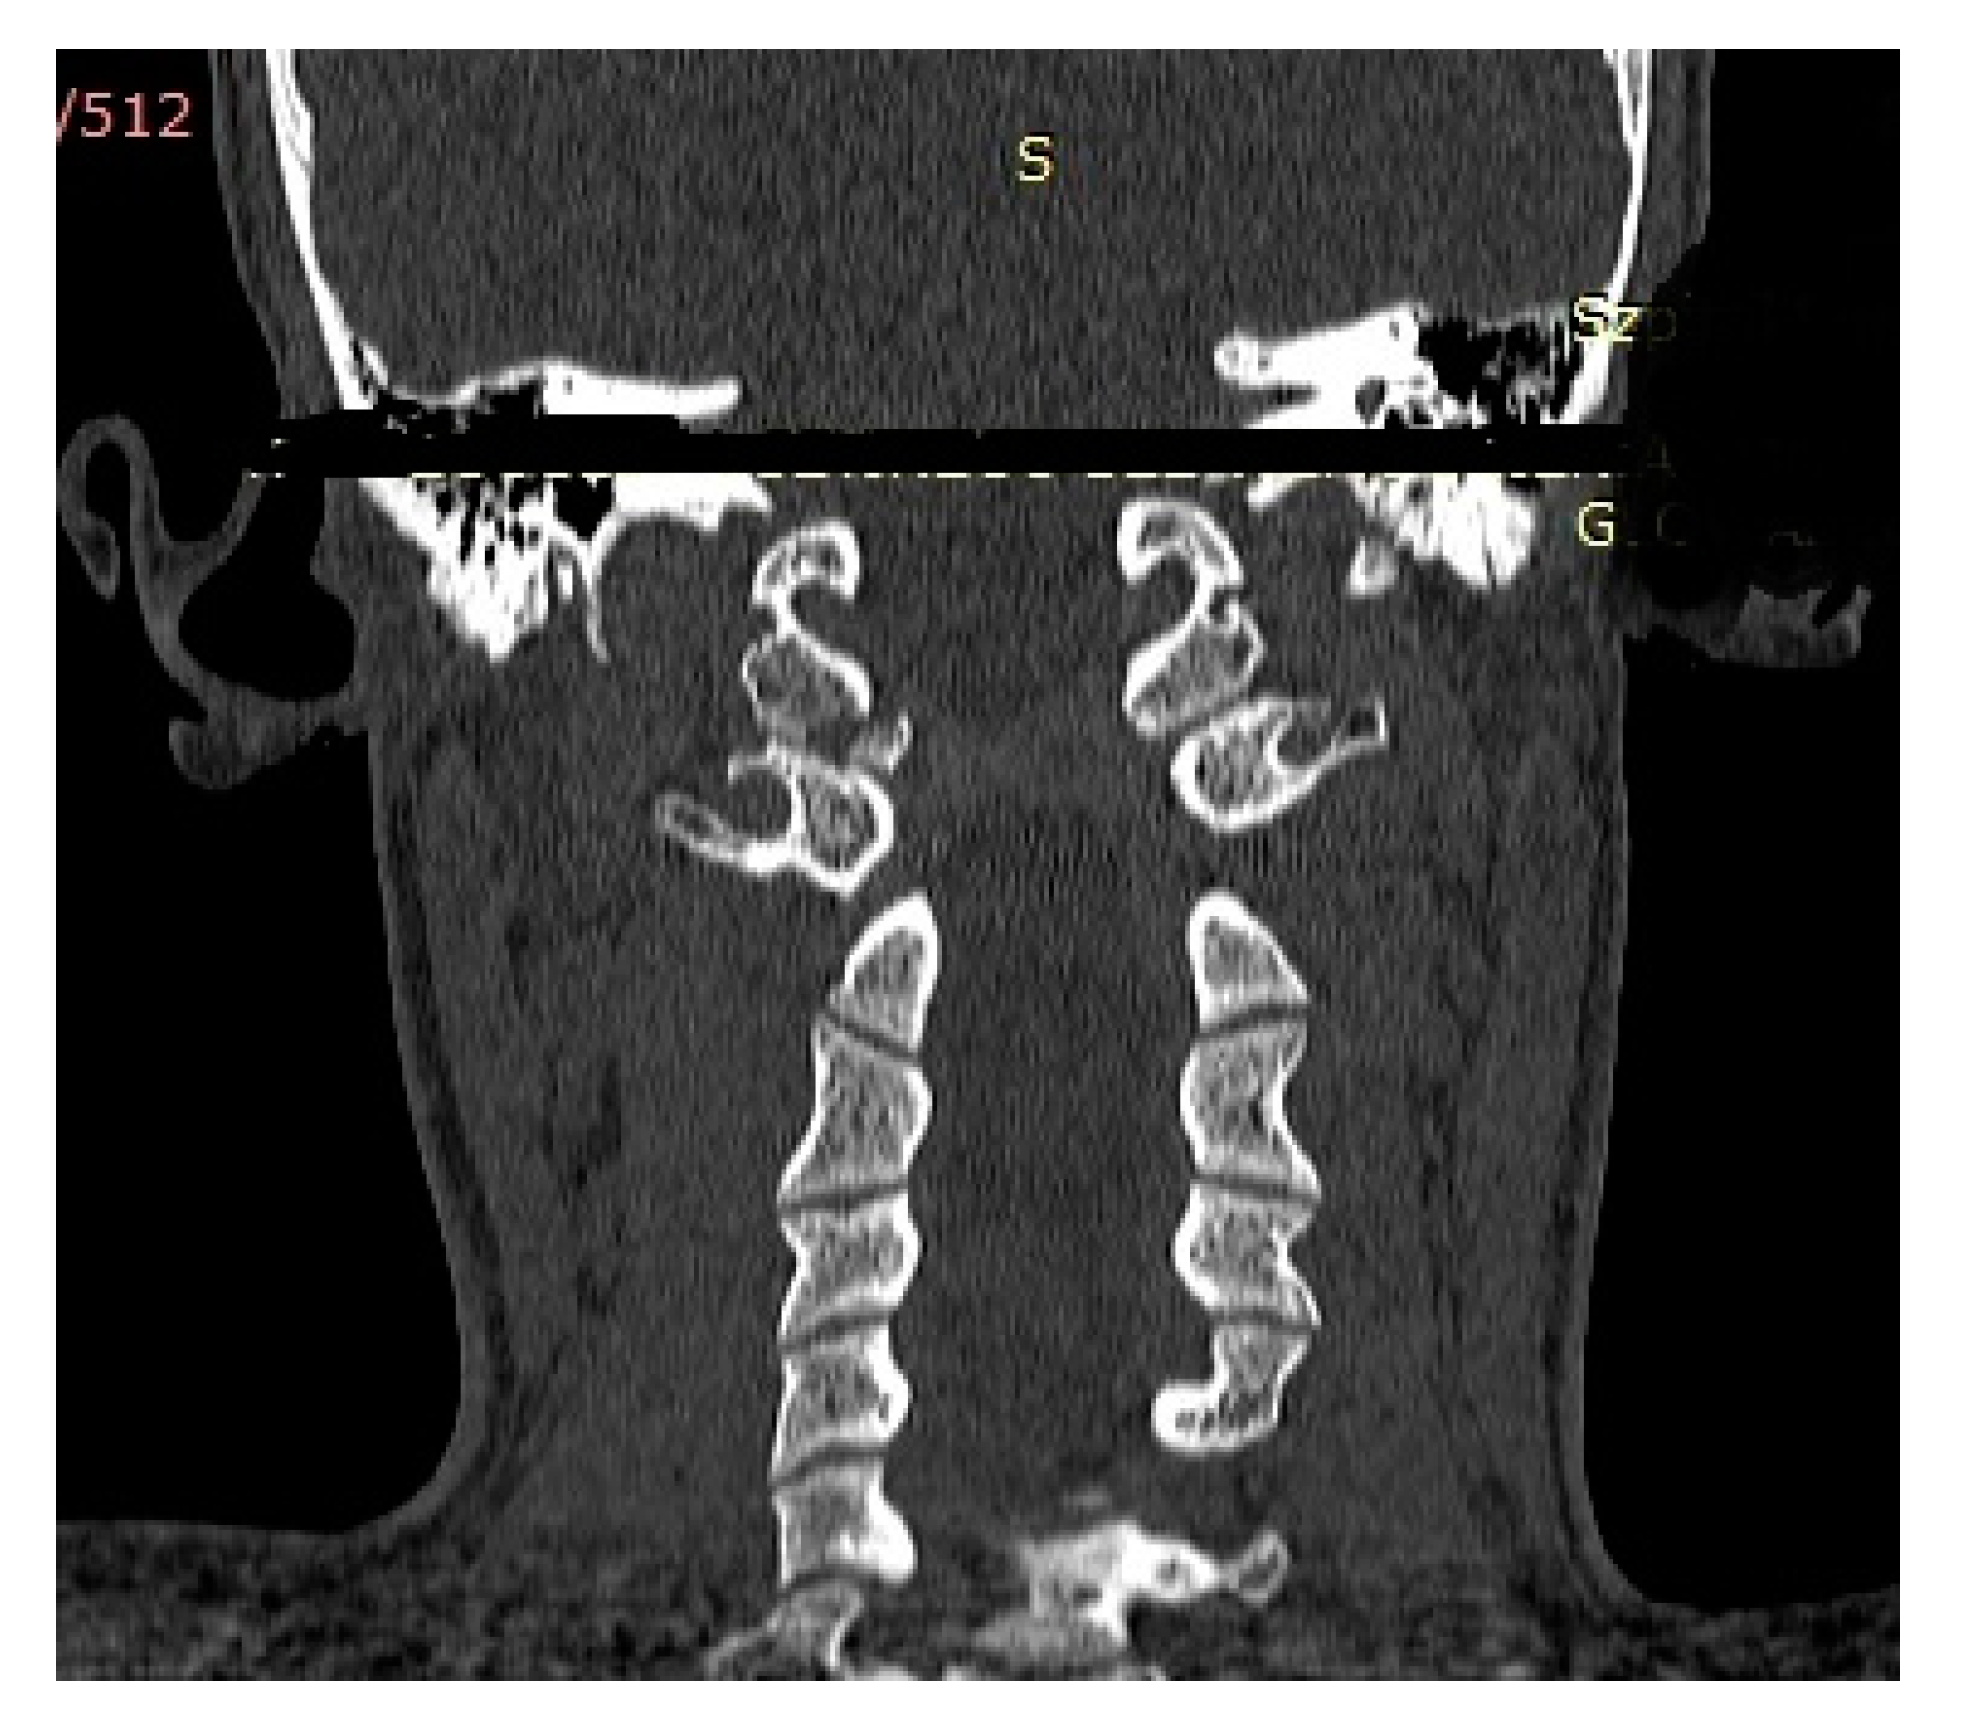

| P.P. | M | 15.2 | III (unstable) | IIB | Road traffic accident (car passenger) | Fracture frontal bone, fracture frontal sinus, contusion of frontal lobe | Halo-vest immobilization: 12.5 weeks |

| K.D. | F | 15 | III (unstable) | IIB | Pedestrian hit by car | Lung contusion, brain concussion, multiple abrasions | Halo-vest immobilization: 13 weeks |

| R.M. | F | 18 | I (unstable) | IIB | Road traffic accident (car passenger) | Pneumothorax, neurogenic vocal cord injury, post-traumatic aphasia | Halo-vest immobilization: 14 weeks |